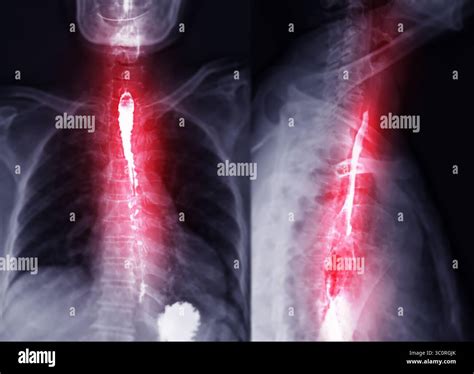

If you have been experiencing persistent difficulty swallowing, chronic heartburn, or unexplained chest pain, your healthcare provider may recommend a Barium Swallow Test to get a clearer picture of what is happening inside your digestive tract. This diagnostic procedure, often referred to as an esophagram, is a specialized type of imaging study that uses X-rays to visualize the upper gastrointestinal tract. By coating the lining of your esophagus, stomach, and the beginning of your small intestine with a chalky liquid called barium, radiologists can identify structural abnormalities or functional issues that might be causing your symptoms.

The barium sulfate used in the procedure acts as a contrast medium. Because it is radio-opaque, it shows up bright white on X-ray images, effectively "painting" the walls of your throat and esophagus. This makes it possible to visualize conditions such as:

- Esophageal strictures or narrowing of the esophagus.

- Tumors or growths along the esophageal wall.